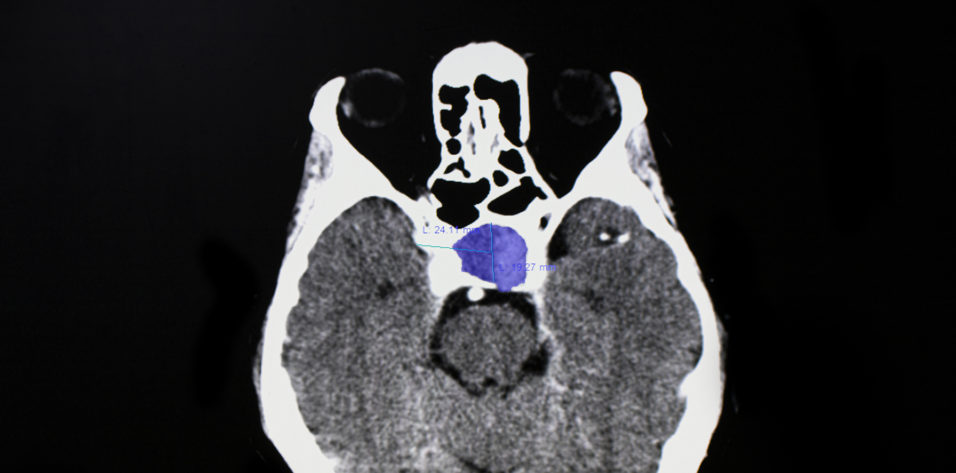

MRI with and without contrast of the brain and/or orbits with attention to the sella is the recommended medium for diagnosis (Figure 2). A patient with a confirmed pituitary macroadenoma should be referred to both neurosurgery and endocrinology. Asymptomatic patients with incidental macroadenomas should receive continued ophthalmologic surveillance because any new visual symptoms strongly indicate a need for surgical intervention. Although there are no established guidelines for the length of ophthalmologic follow-up, lesion size and a progression of visual field defects should inform decisions regarding timeline.

Figure 2. Sagittal midline precontrast T1-weighted MRI showing enlargement of the sella turcica and superior extension of a pituitary macroadenoma (arrow, A). Coronal T1-weighted MRI with contrast showing the optic chiasm stretched and compressed over the mass (arrows, B).